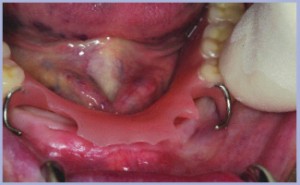

Paziente femminile di anni 66.

La paziente si presenta edentula e da alcuni anni non utilizza la protesi inferiore preesistente (figg. 1-2). Si pianifica l’inserimento di 4 monoimpianti in zona intermentoniera per la stabilizzazione della protesi preesistente. Durante l’intervento la protesi preesistente si mostra utile per la determinazione delle sedi implantari (figg. 3-4).

- Fig.1

- Fig.2